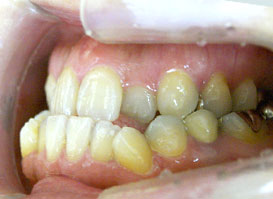

口元症例④

- 性別:女性

- 年齢:23歳

- 治療期間:3年1ヶ月

- 治療前は口元突出感がありましたが、上下左右第一小臼歯を抜歯し、マルチブラケット装置で矯正することで美しいE-Lineとなりました。

- 費用:1,062,600円(税込)

- リスク・副作用:治療後の後戻り・歯根吸収・歯髄壊死・歯肉退縮が生じる場合がございます。